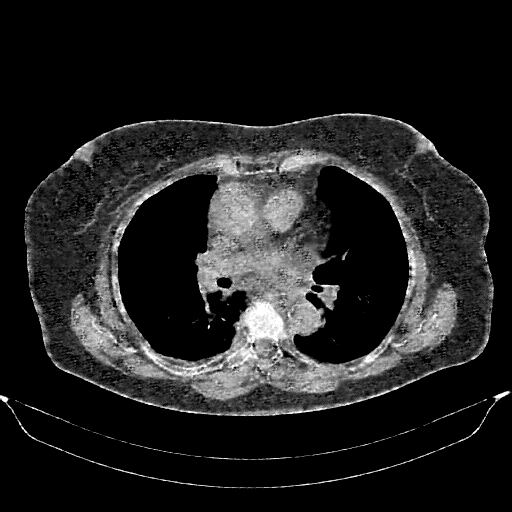

Targeted Slice 70 - Mediastinum Window Analysis (Generated vs Real Venous)

0.655

Mediastinum SSIM

46.3

Mediastinum RMSE

19.4

Mediastinum MAE

Average Mediastinum Window Metrics Across All Slices (161 slices) - Generated vs Real Venous

0.648

Mediastinum SSIM (Avg)

47.9

Mediastinum RMSE (Avg)

20.7

Mediastinum MAE (Avg)

Original VENOUS CT scan

No window - Raw intensity values

Lung window (WL -600, WW 1500 β†’ Low βˆ’1350, High +150)

Mediastinum window (WL 40, WW 400 β†’ Low βˆ’160, High +240)